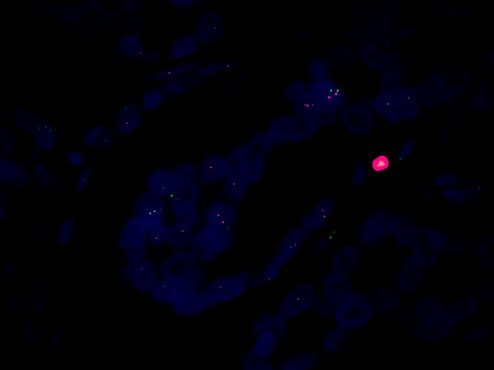

熒光顯微鏡觀察 HER-2:癌癥早篩的關鍵指標

FISH熒光原位雜交是一種先進的顯微鏡技術,可以用于檢測 HER-2 的表達水平。在癌癥早篩中,熒光顯微鏡MF43-N可以用于對熒光染色的細胞進行觀察,然后通過觀察細胞中不同信號點的數量和分布來檢測 HER-2 的表達水平。這種技術可以有效地檢測出 HER-2 過度表達的細胞,為癌癥的早期診斷提供重要依據。

總結起來,熒光顯微鏡MF43-N結合FISH熒光原位雜交技術觀察 HER-2,是癌癥早篩中的有效技術。通過使用這種技術,可以有效地檢測出癌癥的早期跡象,從而提高患者的生存率。